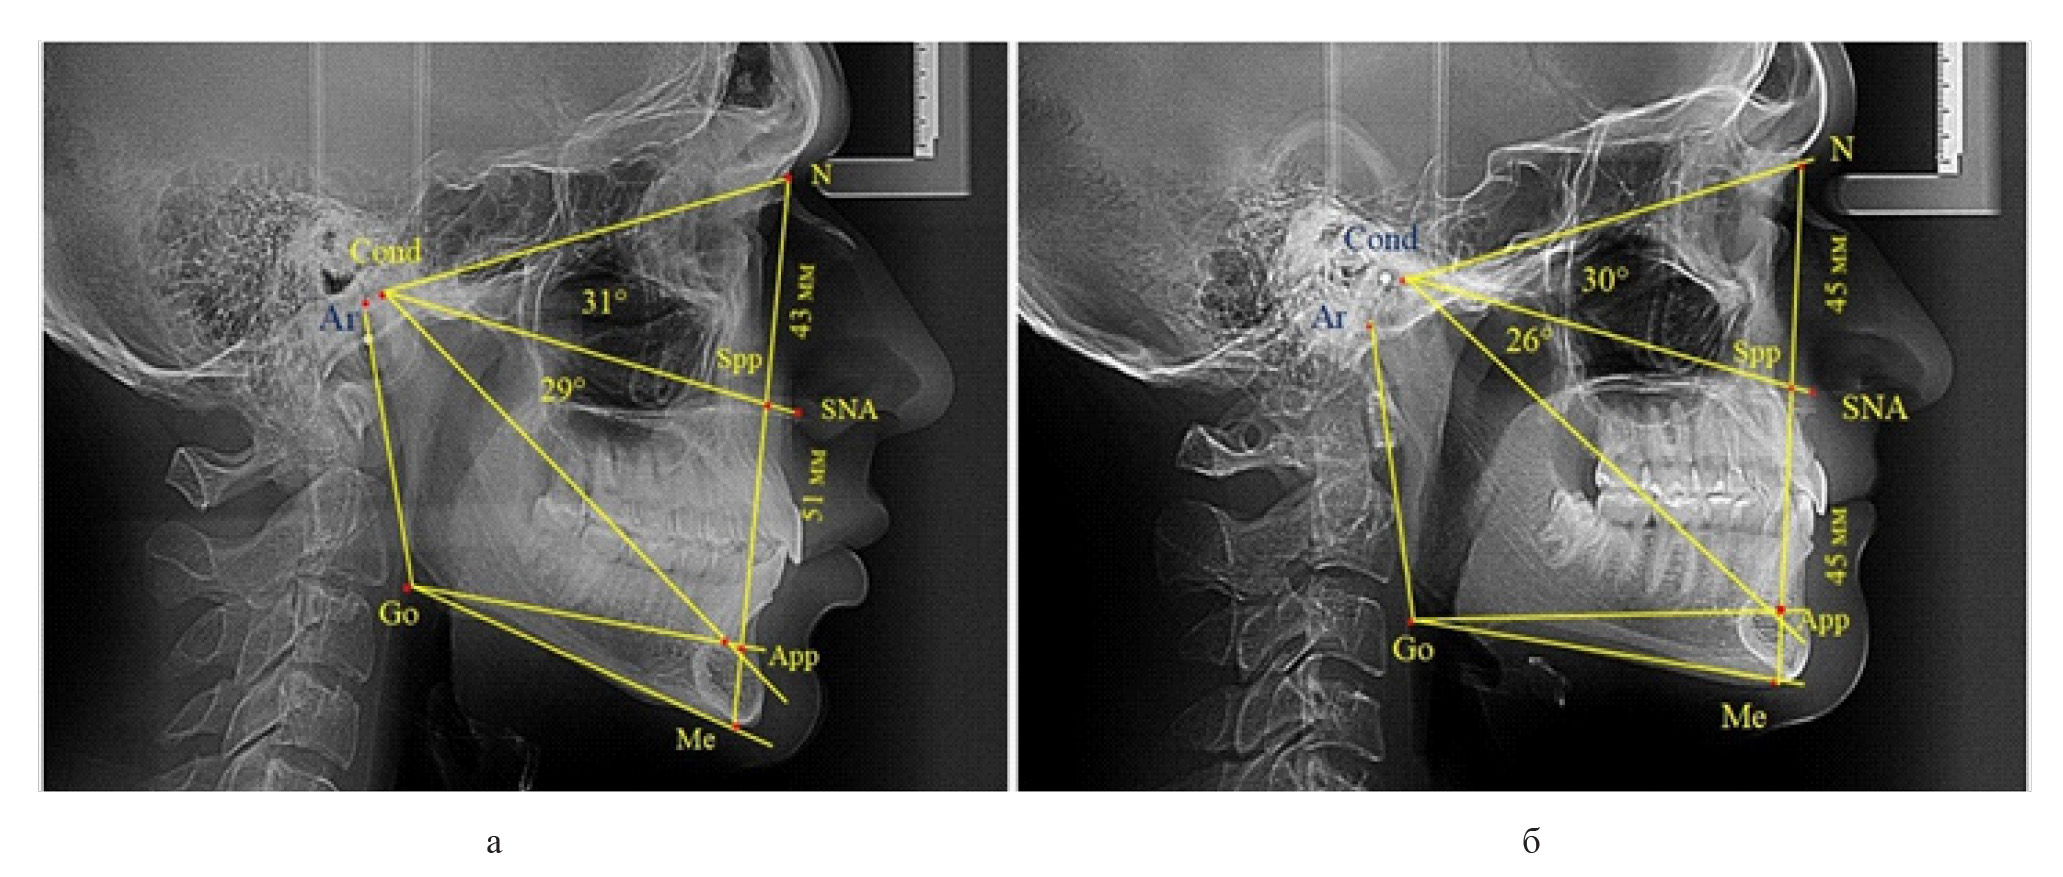

Вертикальная линия передней высоты лица (N-Me), после ее пересечения с линией Cond-SNA, определяла положение точки Spp, при этом вертикаль N-Spp использовалась в качестве оценки высоты назального отдела лица. Продолжение линии Go-Api до пересечения с линией N-Me позволяла определить положение конструктивной точки Арр и оценить линейные размеры гнатической части лица по величине вертикали Spp-Арр (рис. 1).

Рис. 1. Методы оценки основных параметров ТРГ для определения вертикальных размеров лицевого отдела головы

Величина угла назального отдела лица (N-Cond-SNA) в исследуемой группе составила (35,28 ± 0,26)°, а линейные размеры (N-Spp) были (48,82 ± 0,96) мм. Параметры угла гнатической части (SNA-Cond-App) были (29,83 ± 0,54)°, при линейной высоте (49,25 ± 1,31) мм.

Измерения линейных вертикальных параметров показали, что у людей с нейтральным типом роста высота назального отдела составляла (49,53 ± 0,89) мм, а гнатической части – (50,22 ± 0,94) мм и разница в показателях была не достоверной (р ˃ 0,05).

При вертикальным типе роста высота назального отдела составляла (47,79 ± 0,71) мм, а гнатической части – (46,82 ± 0,66) мм.

Для горизонтального типа роста характерна высота назального отдела (47,75 ± 0,75) мм, а гнатической части – (46,49 ± 0,58) мм.